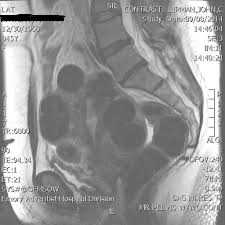

- Магнитно-резонансная томография. Проводят в том случае, если УЗИ оказалось малоинформативным. Отличается метод высокой разрешающей способностью.

| МРТ | Для уточнения диагноза. |

Множественная миома матки на снимке